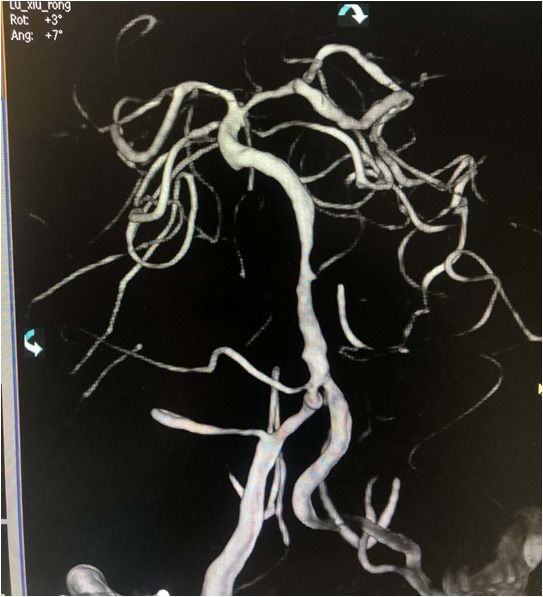

导丝导管通过闭塞部位,经微导管造影,证实在远端真腔内,取栓后M1重度狭窄,球囊扩张。

微导丝微导管通过闭塞部位,经微导管造影,确认在远端真腔。

一把拉通后,前向血流即刻恢复至3级,双侧小脑上动脉、大脑后动脉、基底动脉尖显影。

现基底动脉残余狭窄约40%,观察20min前向血流3级;斑块累及小脑前下动脉;右侧丘脑出血转化,尽可能避免双抗,综合考虑后放弃急诊支架植入,术后给予盐酸替罗非班泵入维持血流稳定。